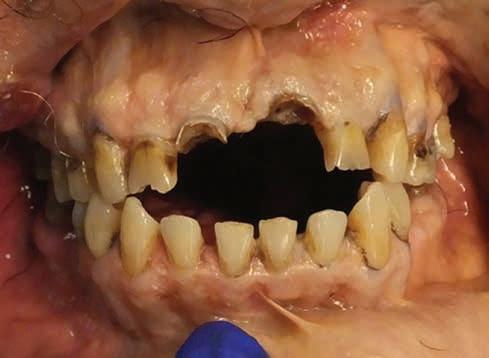

A 44-year-old female patient presented to the general dentistry clinic at the University of California, Los Angeles with a chief complaint of wanting to replace her missing posterior teeth. Her last dental visit was more than 10 years ago. Past medical/surgical history was significant for right sided brain arteriovenous malformation (AVM), seizure disorder secondary to the AVM, stroke, endometrial cancer, and an SRT regimen of 30 Gy in 5 fractions over the span of 6 years. On extraoral examination, the patient reported non-painful clicking on the right temporomandibular joint with mild tenderness of the masseter muscles bilaterally. Intraoral

examination revealed multiple moderately deep carious lesions, abrasion and attrition on the posterior molars and a non-restorable upper right first molar.

Dental Evidence Recovered: Maxilla and Mandible

Maxilla Occlusal View

Mandible Occlusal View

Right Left

Right Lateral View

Left Lateral View

Right Left Left Right